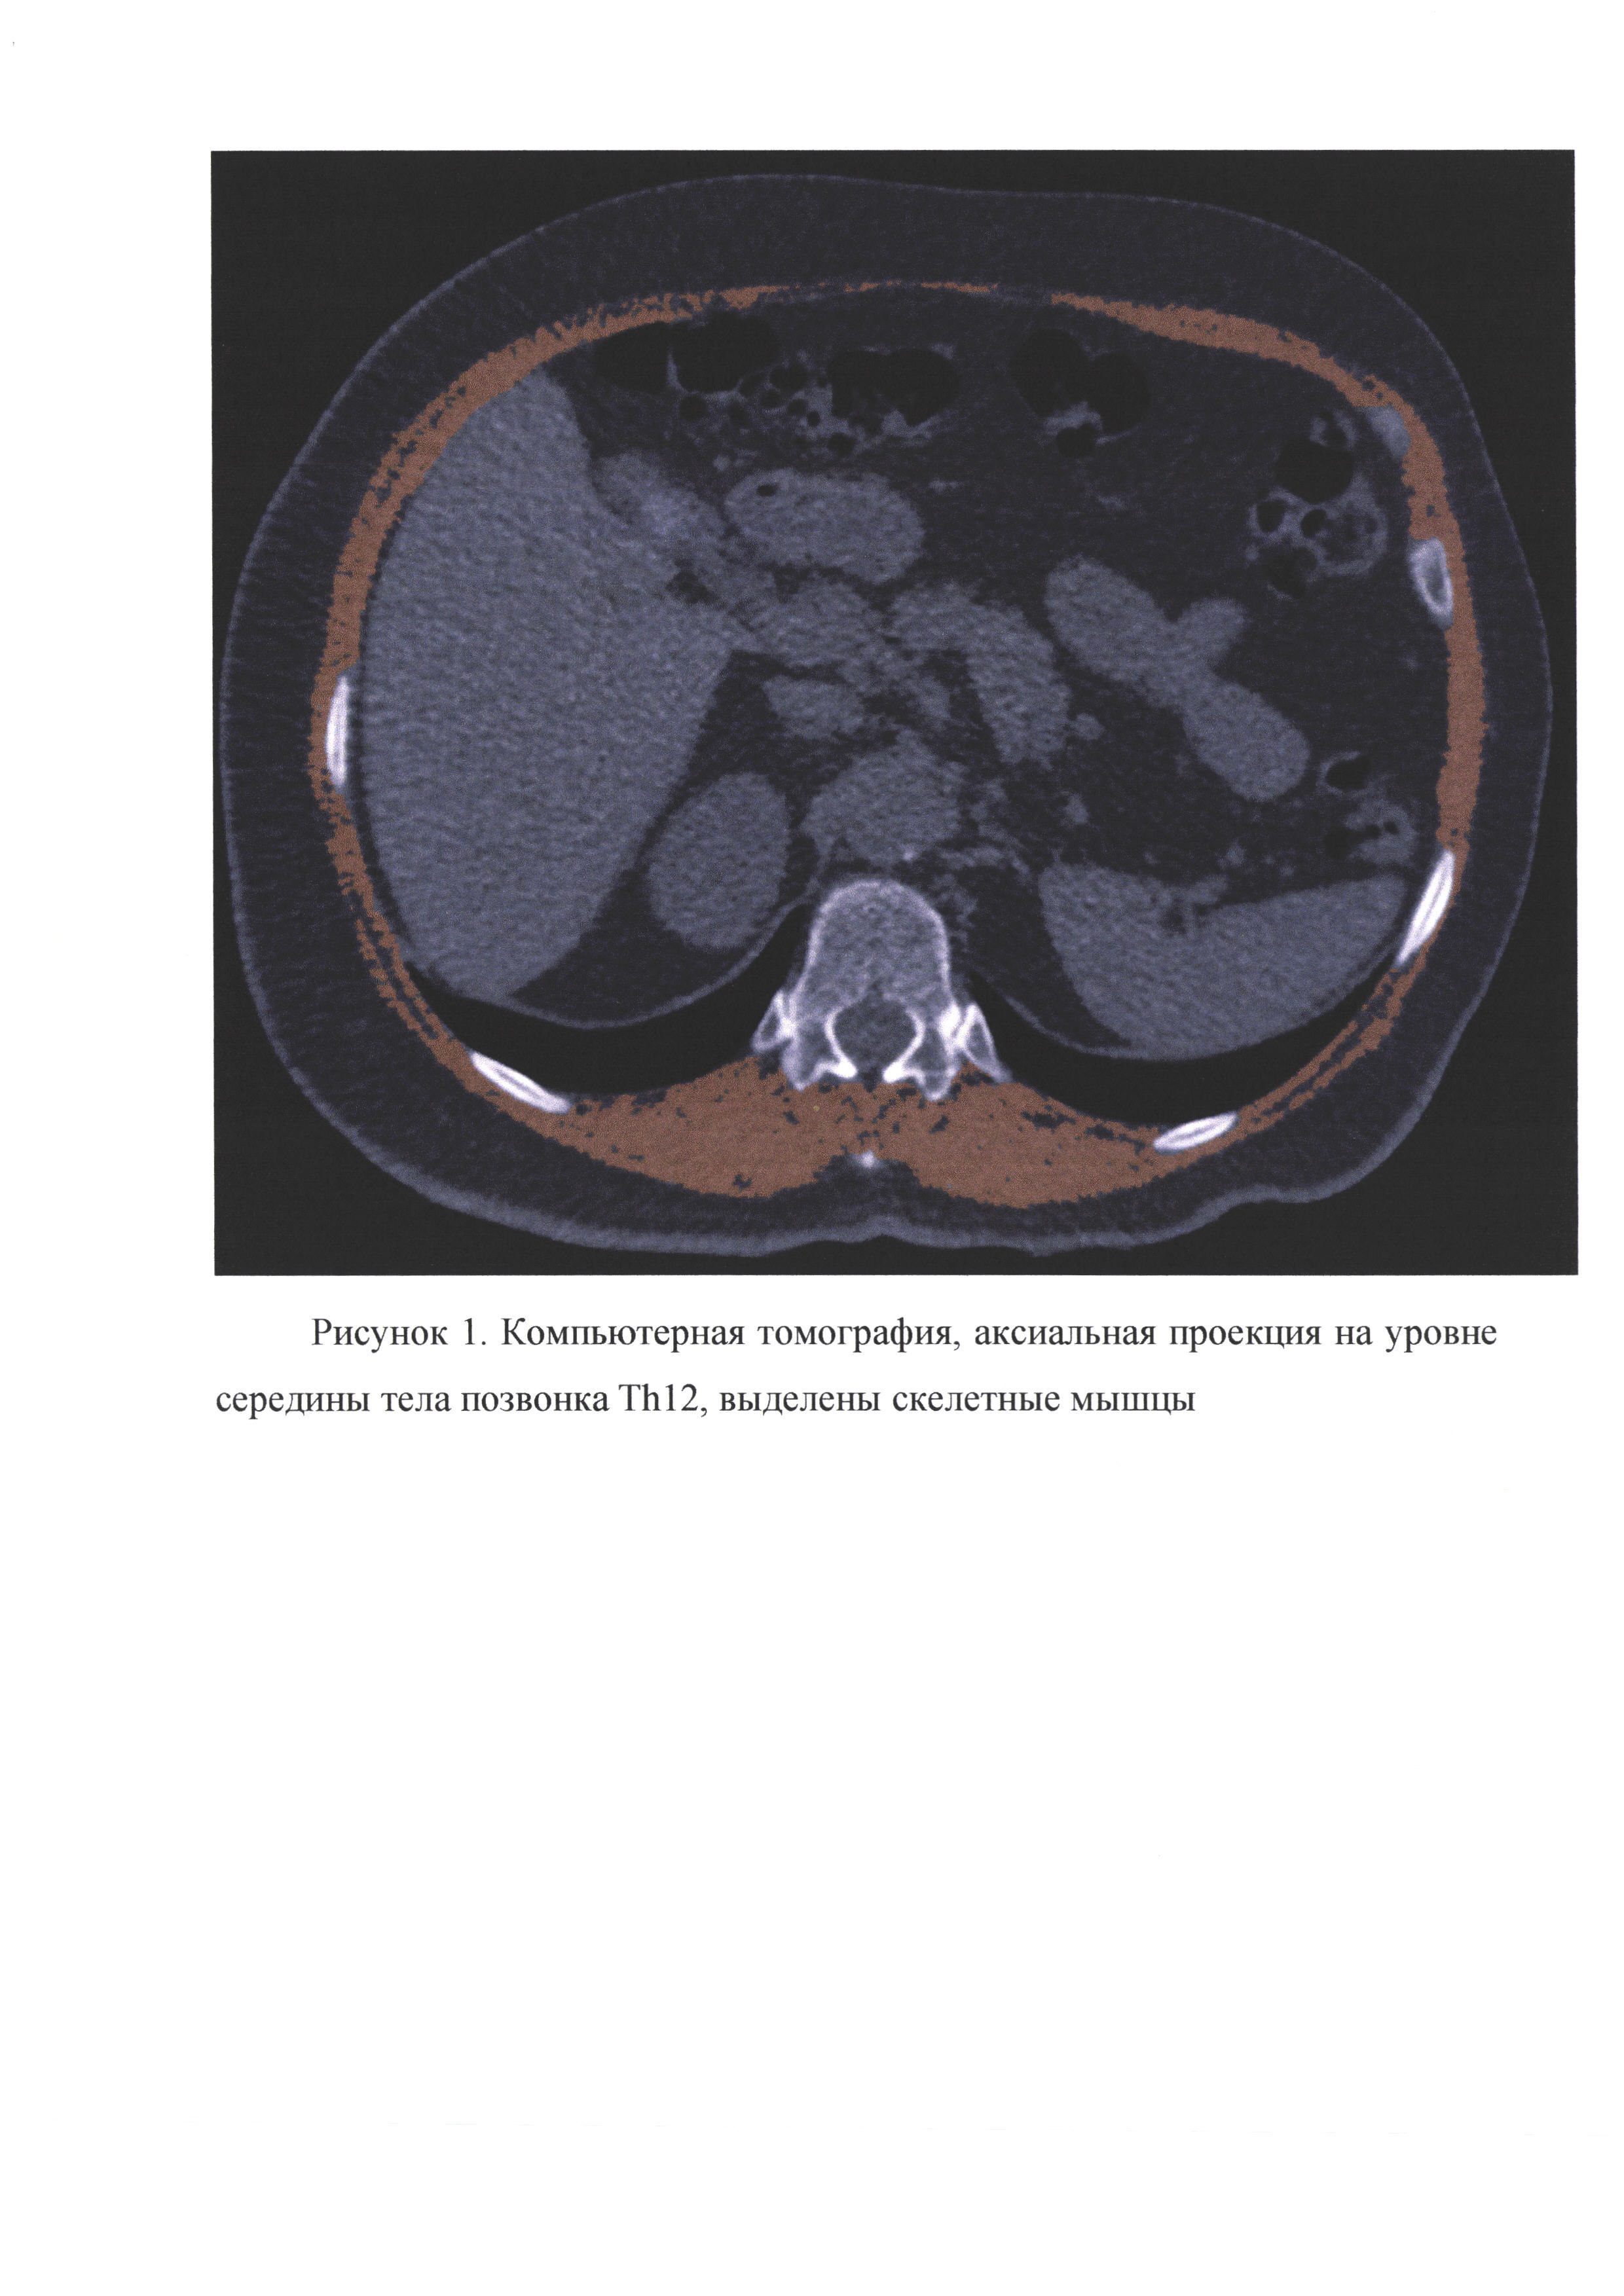

Предлагаемое изобретение относится к медицине, а именно к лучевой диагностике и позволяет определить индекс мышечной массы больного по данным компьютерной томографии при отсутствии информации о росте. Вычисленный таким способом индекс мышечной массы может быть использован для прогноза течения различных заболеваний, риска развития осложений и смертности. Индекс мышечной массы (ИММ) является суррогатным показателем, позволяющим оценить общую массу скелетных мышц человека, снижение которой является одним из критериев диагностики саркопении. Это заболевание представляет собой прогрессирующее и генерализованное заболевание мышечной ткани, которое ассоциировано с увеличением вероятности неблагоприятных событий, таких, как падения, переломы, малоподвижность и смертность. ИММ может определяться по общепринятой методике согласно европейскому консенсусу рабочей группы от 2018 г. (Cruz-Jentoft A.J., Bahat G., Bauer J. et al. Writing Group for the European Working Group on Sarcopenia in Older People 2 (EWGSOP2), and the Extended Group for EWGSOP2. Sarcopenia: revised European consensus on definition and diagnosis // Age Ageing. 2019. Vol. 48. №1. C. 16-31. https://doi.org/10.1093/ageing/afy169). Для этого необходимо по данным компьютерной томографии на аксиальном срезе на уровне позвонка L3 выделить площадь всех скелетных мышц (SMA - skeletal muscle area, см2), а также иметь данные о росте больного (Н, м). Ниже представлена формула для вычисления ИММ - SMIL3 (см2/м2): В литературе различными авторами представлена возможность достоверного определения ИММ и на других уровнях поясничного, а также грудного отдела позвоночника с использованием роста больного (Derstine ВА, Holcombe SA, Ross BE, Wang NC, Su GL, Wang SC. Skeletal muscle cutoff values for sarcopenia diagnosis using T10 to L5 measurements in a healthy US population. Sci Rep. 2018 Jul 27; 8(1):11369. doi: 10.103 8/s41598-018-29825-5.). Однако, если пациент находится в тяжелом состоянии или в целом отсутствует возможность нахождения в вертикальном положении для измерения роста (неврологические нарушения, заболевания опорно-двигательного аппарата), то определение ИММ по общепринятой методике не представляется возможным. В то же время определение этого показателя может потребоваться у таких больных как в клинической практике, так и при проведении научных исследований, так как он обладает важным прогностическим значением при различных заболеваниях (злокачественный онкологический процесс, хронические заболевания сердечно-сосудистой и респираторной системы, цирроз и др.), а также определяет риск развития послеоперационных осложнений. В частности, доказано, что саркопения является одним из факторов риска тяжелого течения COVID19 и повышенной смертности (Siahaan YMT, Hartoyo V, Hariyanto TI, Kurniawan A. Coronavirus disease 2019 (Covid-19) outcomes in patients with sarcopenia: A meta-analysis and meta-regression. Clin Nutr ESPEN. 2022; 48:158-166. doi:10.1016/j.clnesp.2022.01.016). Таким образом, общепринятая методика, использующая рост пациента, не позволяет определить ИММ при изучении прогностической роли саркопении у ряда больных в том числе с социально значимыми заболеваниями. В качестве аналога взята общепринятая методика определения ИММ на уровне позвонка L3 с использованием роста пациента (Cruz-Jentoft A.J., Bahat G., Bauer J. et al. Writing Group for the European Working Group on Sarcopenia in Older People 2 (EWGSOP2), and the Extended Group for EWGSOP2. Sarcopenia: revised European consensus on definition and diagnosis // Age Ageing. 2019. Vol. 48. №1. C. 16-31. https://doi.Org/10.1093/ageing/afy169) Недостатки: 1. необходимы данные KT на уровне позвонка L3 (при проведении КТ органов грудной клетки этот уровень не входит в область сканирования), 2. необходимы данные о росте больного. Ближайшие аналоги: 1. методика оценки мышечной массы на уровне позвонка Th12 только по площади мышц (Menozzi R, Valoriani F, Prampolini F, et al. Impact of sarcopenia in SARS-CoV-2 patients during two different epidemic waves. Clin Nutr ESPEN. 2022; 47:252-259. doi:10.1016/j.clnesp.2021.12.001; недостаток - отсутствие учета антропометрических параметров пациента не позволяет проводить статистически значимые исследования; 2. методика оценки мышечной массы на уровне позвонка Th12 с использованием роста больного (Nemec U, Heidinger В, Sokas С, Chu L, Eisenberg RL. Diagnosing Sarcopenia on Thoracic Computed Tomography: Quantitative Assessment of Skeletal Muscle Mass in Patients Undergoing Transcatheter Aortic Valve Replacement. Acad Radiol. 2017; 24(9):1154-1161. doi:10.1016/j.acra.2017.02.008; недостаток - необходимы данные о росте больного; 3. методика оценки мышечной массы на уровне позвонка Th12 с использованием длины грудного отдела позвоночника (Башков А.Н., Сушко А.И., Григорьева О.О., Шейх Ж.В., Удалов Ю.Д., Шикунов Д.А. Индекс мышечной массы на уровне позвонка Th12 как прогностический фактор летального исхода у пациентов с пневмонией, вызванной sars-cov2 // Медицинская радиология и радиационная безопасность. 2021. №. 1. С. 49-53. DOI: https://doi.org/10.12737/1024-6177-2021-66-1-49-53); недостатки - измерение длины грудного отдела позвоночника по данным КТ трудоемко, особенно у пациентов со сколиозом, в случае выраженного физиологического кифоза можно ожидать слабую корреляцию длины грудного отдела позвоночника и роста больного. Задачи: 1. Разработать способ определения ИММ на уровне позвонка Th12 по данным компьютерной томографии с использованием вместо роста пациента высоты грудного отдела позвоночника. Способ осуществляют следующим образом. Для решения поставленной задачи предложено определять площадь всех скелетных мышц (SMA - skeletal muss area, см2) на уровне середины тела позвонка Th12 на аксиальном срезе КТ исследования с помощью сегментации с использованием интервала плотности от -29HU до 150HU (рис. 1). Середина тела позвонка Th12 может быть точно установлена в сагиттальной плоскости. В этой же плоскости проводится измерение высоты грудного отдела позвоночника (HTh1-12, м) как кратчайшее расстояние между наиболее краниально расположенной точкой тела позвонка Th1 и плоскостью, проходящей перпендикулярно оси сканирования через наиболее каудально расположенную точку тела позвонка Th12 (рис. 2). В итоге индекс мышечной массы SMITh12 (см2/м2) вычисляется по формуле: Коэффициент 100 в формуле необходим для удобства оперирования данными, так как позволяет получать целые числа. По отношению к ближайшим аналогам заявляемый способ имеет следующие преимущества: - появляется возможность определения индекса мышечной массы на уровне позвонка Th12 при отсутствии данных о росте больного, когда он по различным медицинским причинам не может принять вертикальное положение; - появляется возможность определения индекса мышечной массы на уровне позвонка Th12 у пациентов, которым проводились как КТ органов грудной клетки, так и брюшной полости, так как уровень позвонка Th12 входит в область сканирования в обоих случаях; - определение индекса мышечной массы на уровне позвонка Th12 с использованием только данных КТ позволяет использовать предложенный метод как основу для создания программного обеспечения для определения ИММ с помощью «машинного зрения» на основе возможностей искусственного интеллекта. Заявляемый способ определения индекса мышечной массы апробирован клинически. В случайном порядке была набрана группа из 257 пациентов (120 мужчин и 137 женщин) в возрасте от 36 до 86 лет, которым было проведено КТ органов грудной клетки и брюшной полости. Каждому пациенту были определены ИММ на уровне позвонка Th12 с использованием высоты грудного отдела позвоночника согласно разработанной нами методике и роста. Также определялся ИММ по общепринятой методике на уровне позвонка L3 с использованием роста больного. В результате продемонстрирована очень высокая степень корреляции между ИММ на уровне позвонка Th12 с использованием высоты грудного отдела позвоночника (предложенная нами методика) и роста (r=0,947, р<0,001), что подтверждает возможность использования вместо роста пациента высоты грудного отдела позвоночника. Также высокая степень корреляции выявлена между ИММ на уровне позвонка Th12 с использованием высоты грудного отдела позвоночника (предложенная нами методика) и ИММ на уровне позвонка L3 (общепринятый аналог) (r=0,778, р<0,001). Разработанный способ в виду своей эффективности и относительной простоте исполнения может служить альтернативой методикам определения индекса мышечной массы с использованием роста пациентов, у которых невозможно измерить рост или при проведении научных исследований на основе большого количества данных КТ при отсутствии информации о росте больных.